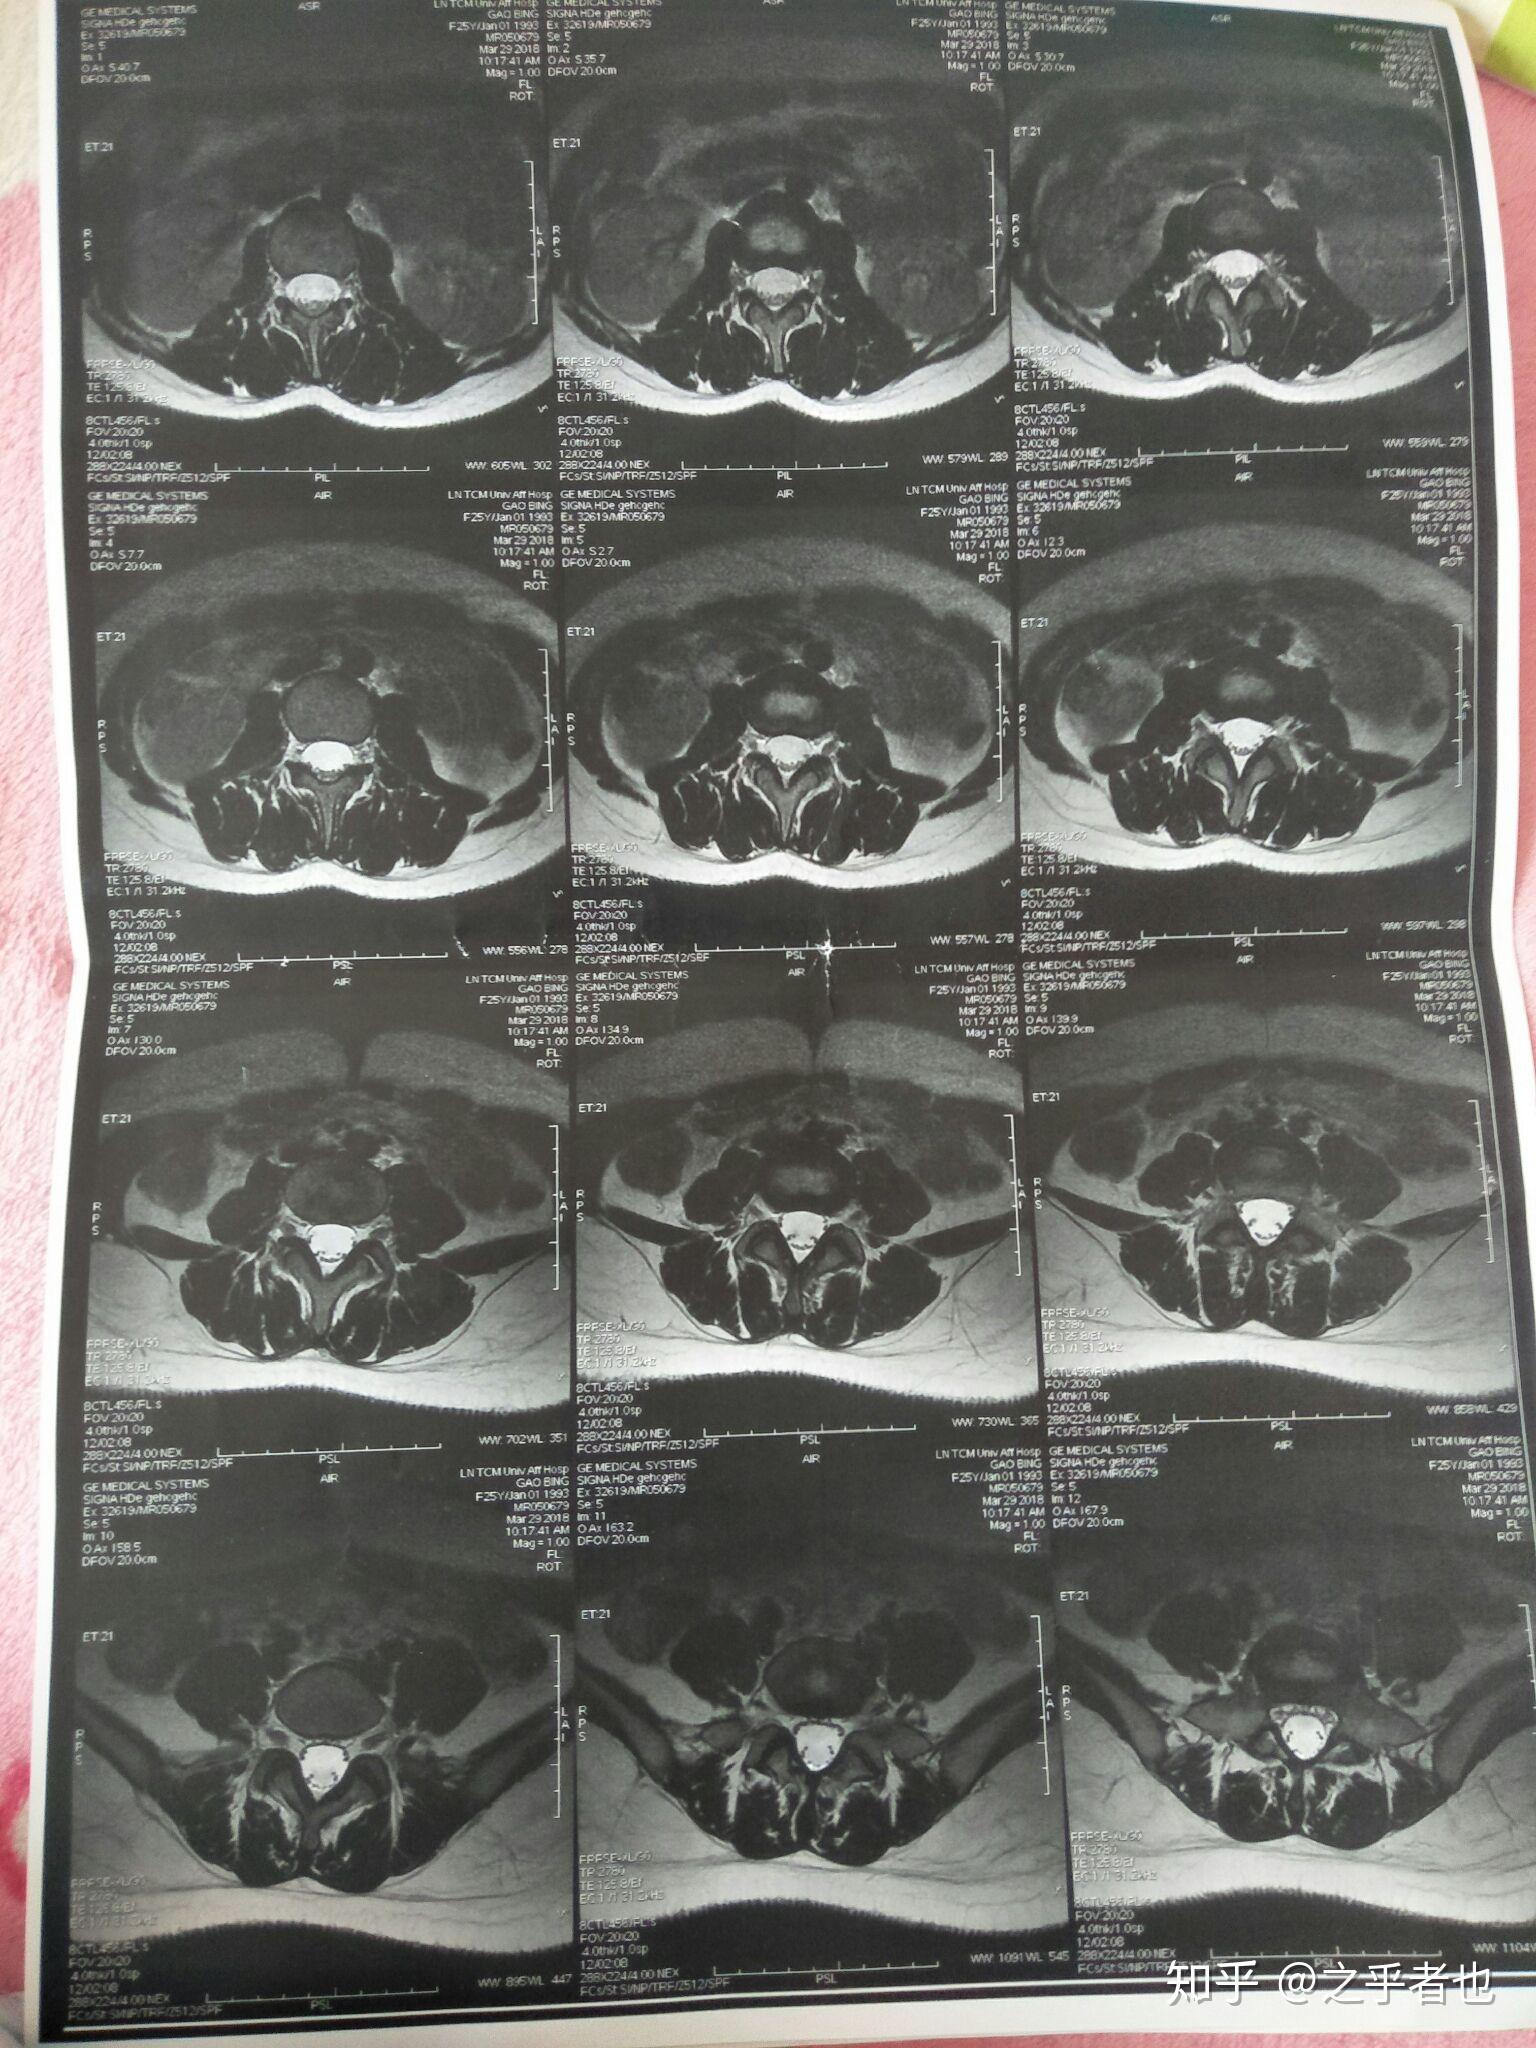

请各位大神看看这个腰椎的核磁片子有没有什么问题谢谢

图片尺寸1536x2048